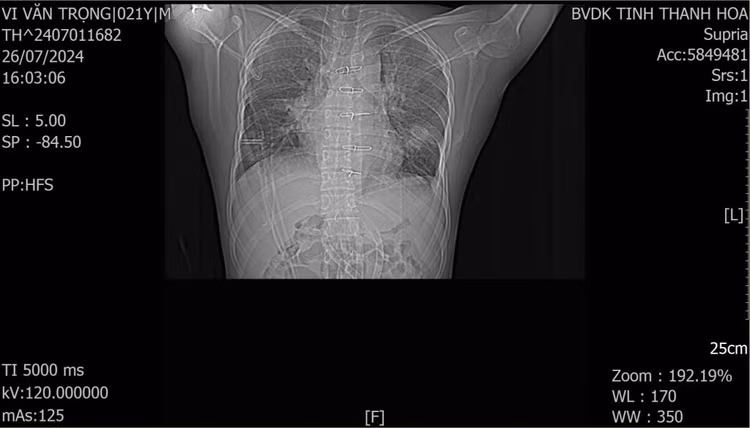

Bệnh nhân được chẩn đoán sơ bộ ban đầu là sốc mất máu do chấn thương ngực kín, suy hô hấp, suy tuần hoàn do tràn khí áp lực khoang màng phổi trái. Ngay lập tức, bệnh nhân được các bác sĩ cấp cứu hồi sức tim phổi, dẫn lưu màng phổi trái để giải phóng khí và đặt nội khí quản (kết quả chụp phim X-quang phổi của tuyến trước có tràn khí màng phổi trái).

| Hình ảnh phim chụp CLVT phổi của bệnh nhân sau 1 tuần phẫu thuật |